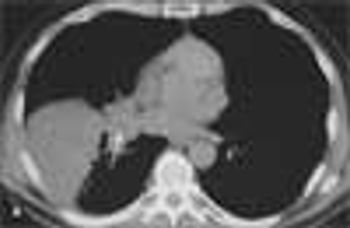

During the evaluation of a 61-year-old man who had sustained mild head and upper trunk injuries in a car accident, a right lower lobe consolidation was noted on the chest radiograph. There was no evidence of rib fracture. A chest CT scan with contrast showed a hilar mass that obstructed the lateral segmental bronchi of the right lower lobe. Atelectasis of the posteromedial segments of the right lower lobe and ipsilateral subcarinal adenopathy were also noted.